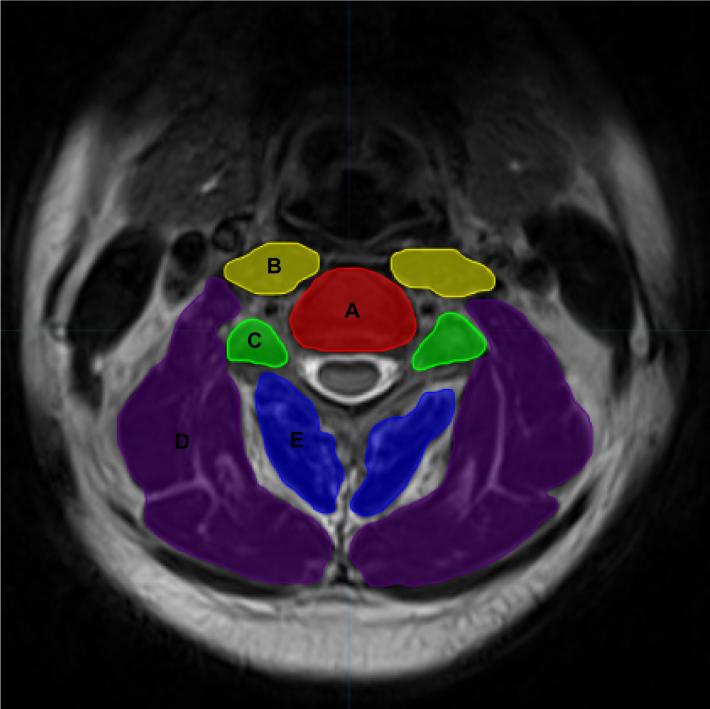

METHODS: This study recruited young and middle-aged participants (18-45 years), including both cervical instability patients and healthy controls, through the Spine Department Outpatient Clinic of Wangjing Hospital, China Academy of Chinese Medical Sciences, as well as community-based recruitment. All participants underwent cervical magnetic resonance imaging examinations. On the axial magnetic resonance imaging images, five key anatomical structures were manually annotated: intervertebral disc, facet, prevertebral muscle, deep muscle group in the back of the neck, and superficial muscle group in the back of the neck. A deep learning algorithm was then employed to develop a predictive model for cervical instability, utilizing both the original images and the delineated regions of interest. Finally, the model's predictive performance was systematically evaluated and validated.